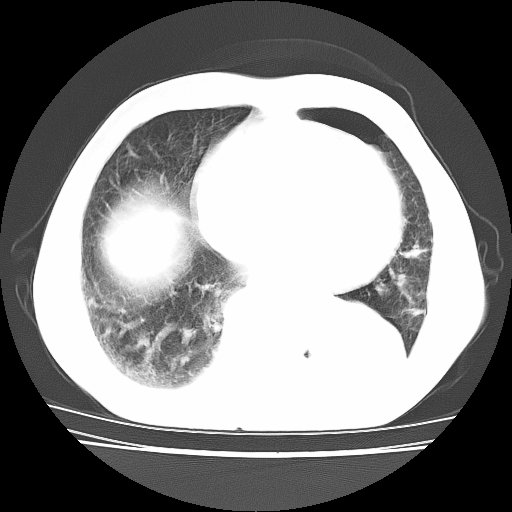

男,71岁,咳嗽,气喘10年,再发并咯血.胸片见气胸

考虑  左肺中心型肺癌伴阻塞性肺炎,肺不张,纵膈淋巴结肿大。慢支炎,肺气肿,左侧气胸肺压缩5%

左侧中央型肺癌伴纵膈淋巴结转移。

左肺中心型肺癌伴阻塞性肺炎,肺不张,纵膈淋巴结肿大

1)考虑左肺中心型肺癌伴阻塞性肺炎、左肺下叶肺不张、左侧肺气肿,纵膈淋巴结转移。2)左侧气胸(肺组织压缩约5%)。

左肺中心型肺癌伴阻塞性肺不张、肺气肿 。

1)考虑左肺中心型肺癌伴阻塞性肺炎、左肺下叶肺不张、左侧肺气肿,纵膈淋巴结转移。2)左侧气胸。